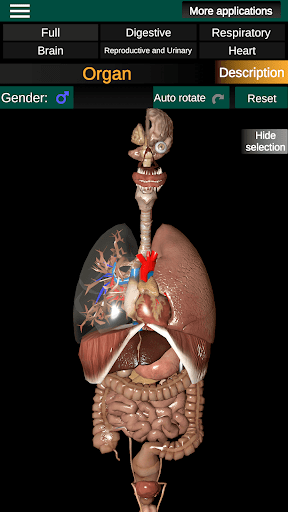

Shows a 3D anatomical model of the main organs of the human body and a description of each one.

What's in the app?

* Easy to access and navigate (zoom, 3D rotation).

* Hide or show information.

* Compare male and female organs.

* Descriptions of each organ.